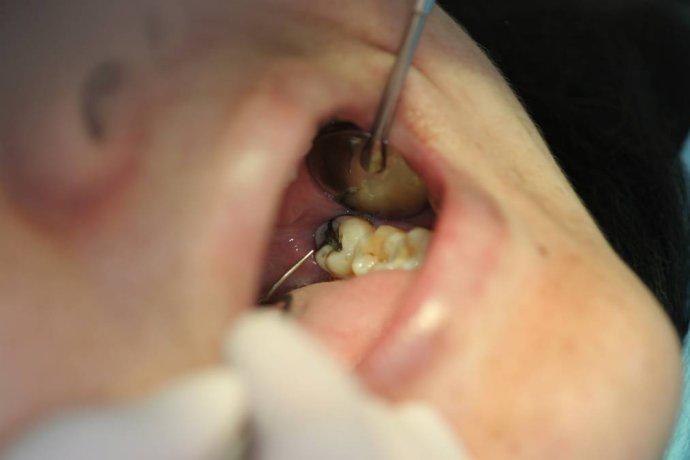

洗牙专业术语叫洁治术,是使用超声或手工把牙齿周围的牙石和菌斑去除同时也使口腔视觉上干净,无异味,洗牙是维持牙周健康、预防牙龈炎和牙周炎发生或复发的重要措施。

现在最通行的方法是超声波洁治。

超声波洁治是超声洁牙机由超声波发生器和换能器组成,发生器发出电磁振荡,并将功率放大,换能器将高频电能转换为超声振动,振动频率达2万至4.5万赫兹。通过换能器上工作头的高频振荡,将附着于牙面上的牙石去除。

超声洁牙机的工作头有多种形状,如尖圆型和扁平型等,可根据牙石的大小、部位等来选择合适的工作头。

此外,超声洁牙机上还带有喷水系统,在启动工作头超声振动时,喷水系统同时向工作头喷水,形成气雾。

一方面起到冷却工作头的作用,另一重要方面是形成空穴作用,即在喷雾的水滴内有细微的真空泡迅速塌陷而产生能量,对牙石、菌斑等产生冲刷作用,并将震碎的牙石和血污冲走。

超声洁治的优点是省时省力,一般一小时左右可以完成全口牙齿的龈上洁治术。

超声洁治后,还应用探针仔细检查有无遗漏的的牙石,如果遗留有一些细小的牙石和邻面的牙石,还应用手动器械将其清除干净。